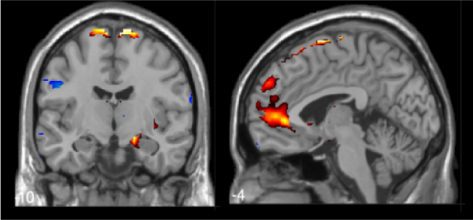

Sur la trace de ces neurones qui nous rendent sociables

CP_Bellone122021_bandeau.jpg